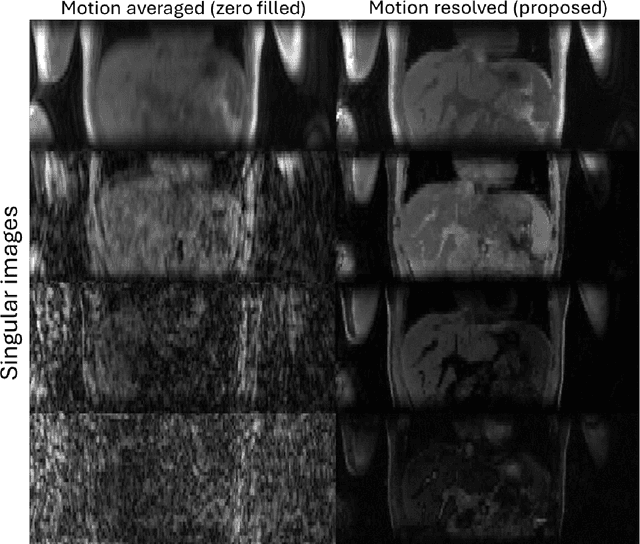

Purpose: To develop an MRI technique for free-breathing 3D whole-liver quantification of water T1, water T2, proton density fat fraction (PDFF), R2*. Methods: An Eight-echo spoiled gradient echo pulse sequence with spiral readout was developed by interleaving inversion recovery and T2 magnetization preparation. We propose a neural network based on a 4D and a 3D implicit neural representation (INR) which simultaneously learns the motion deformation fields and the static reference frame MRI subspace images respectively. Water and fat singular images were separated during network training, with no need of performing retrospective water-fat separation. T1, T2, R2* and proton density fat fraction (PDFF) produced by the proposed method were validated in vivo on 10 healthy subjects, using quantitative maps generated from conventional scans as reference. Results: Our results showed minimal bias and narrow 95% limits of agreement on T1, T2, R2* and PDFF values in the liver compared to conventional breath-holding scans. Conclusions: INR-MRF enabled co-registered 3D whole liver T1, T2, R2* and PDFF mapping in a single free-breathing scan.